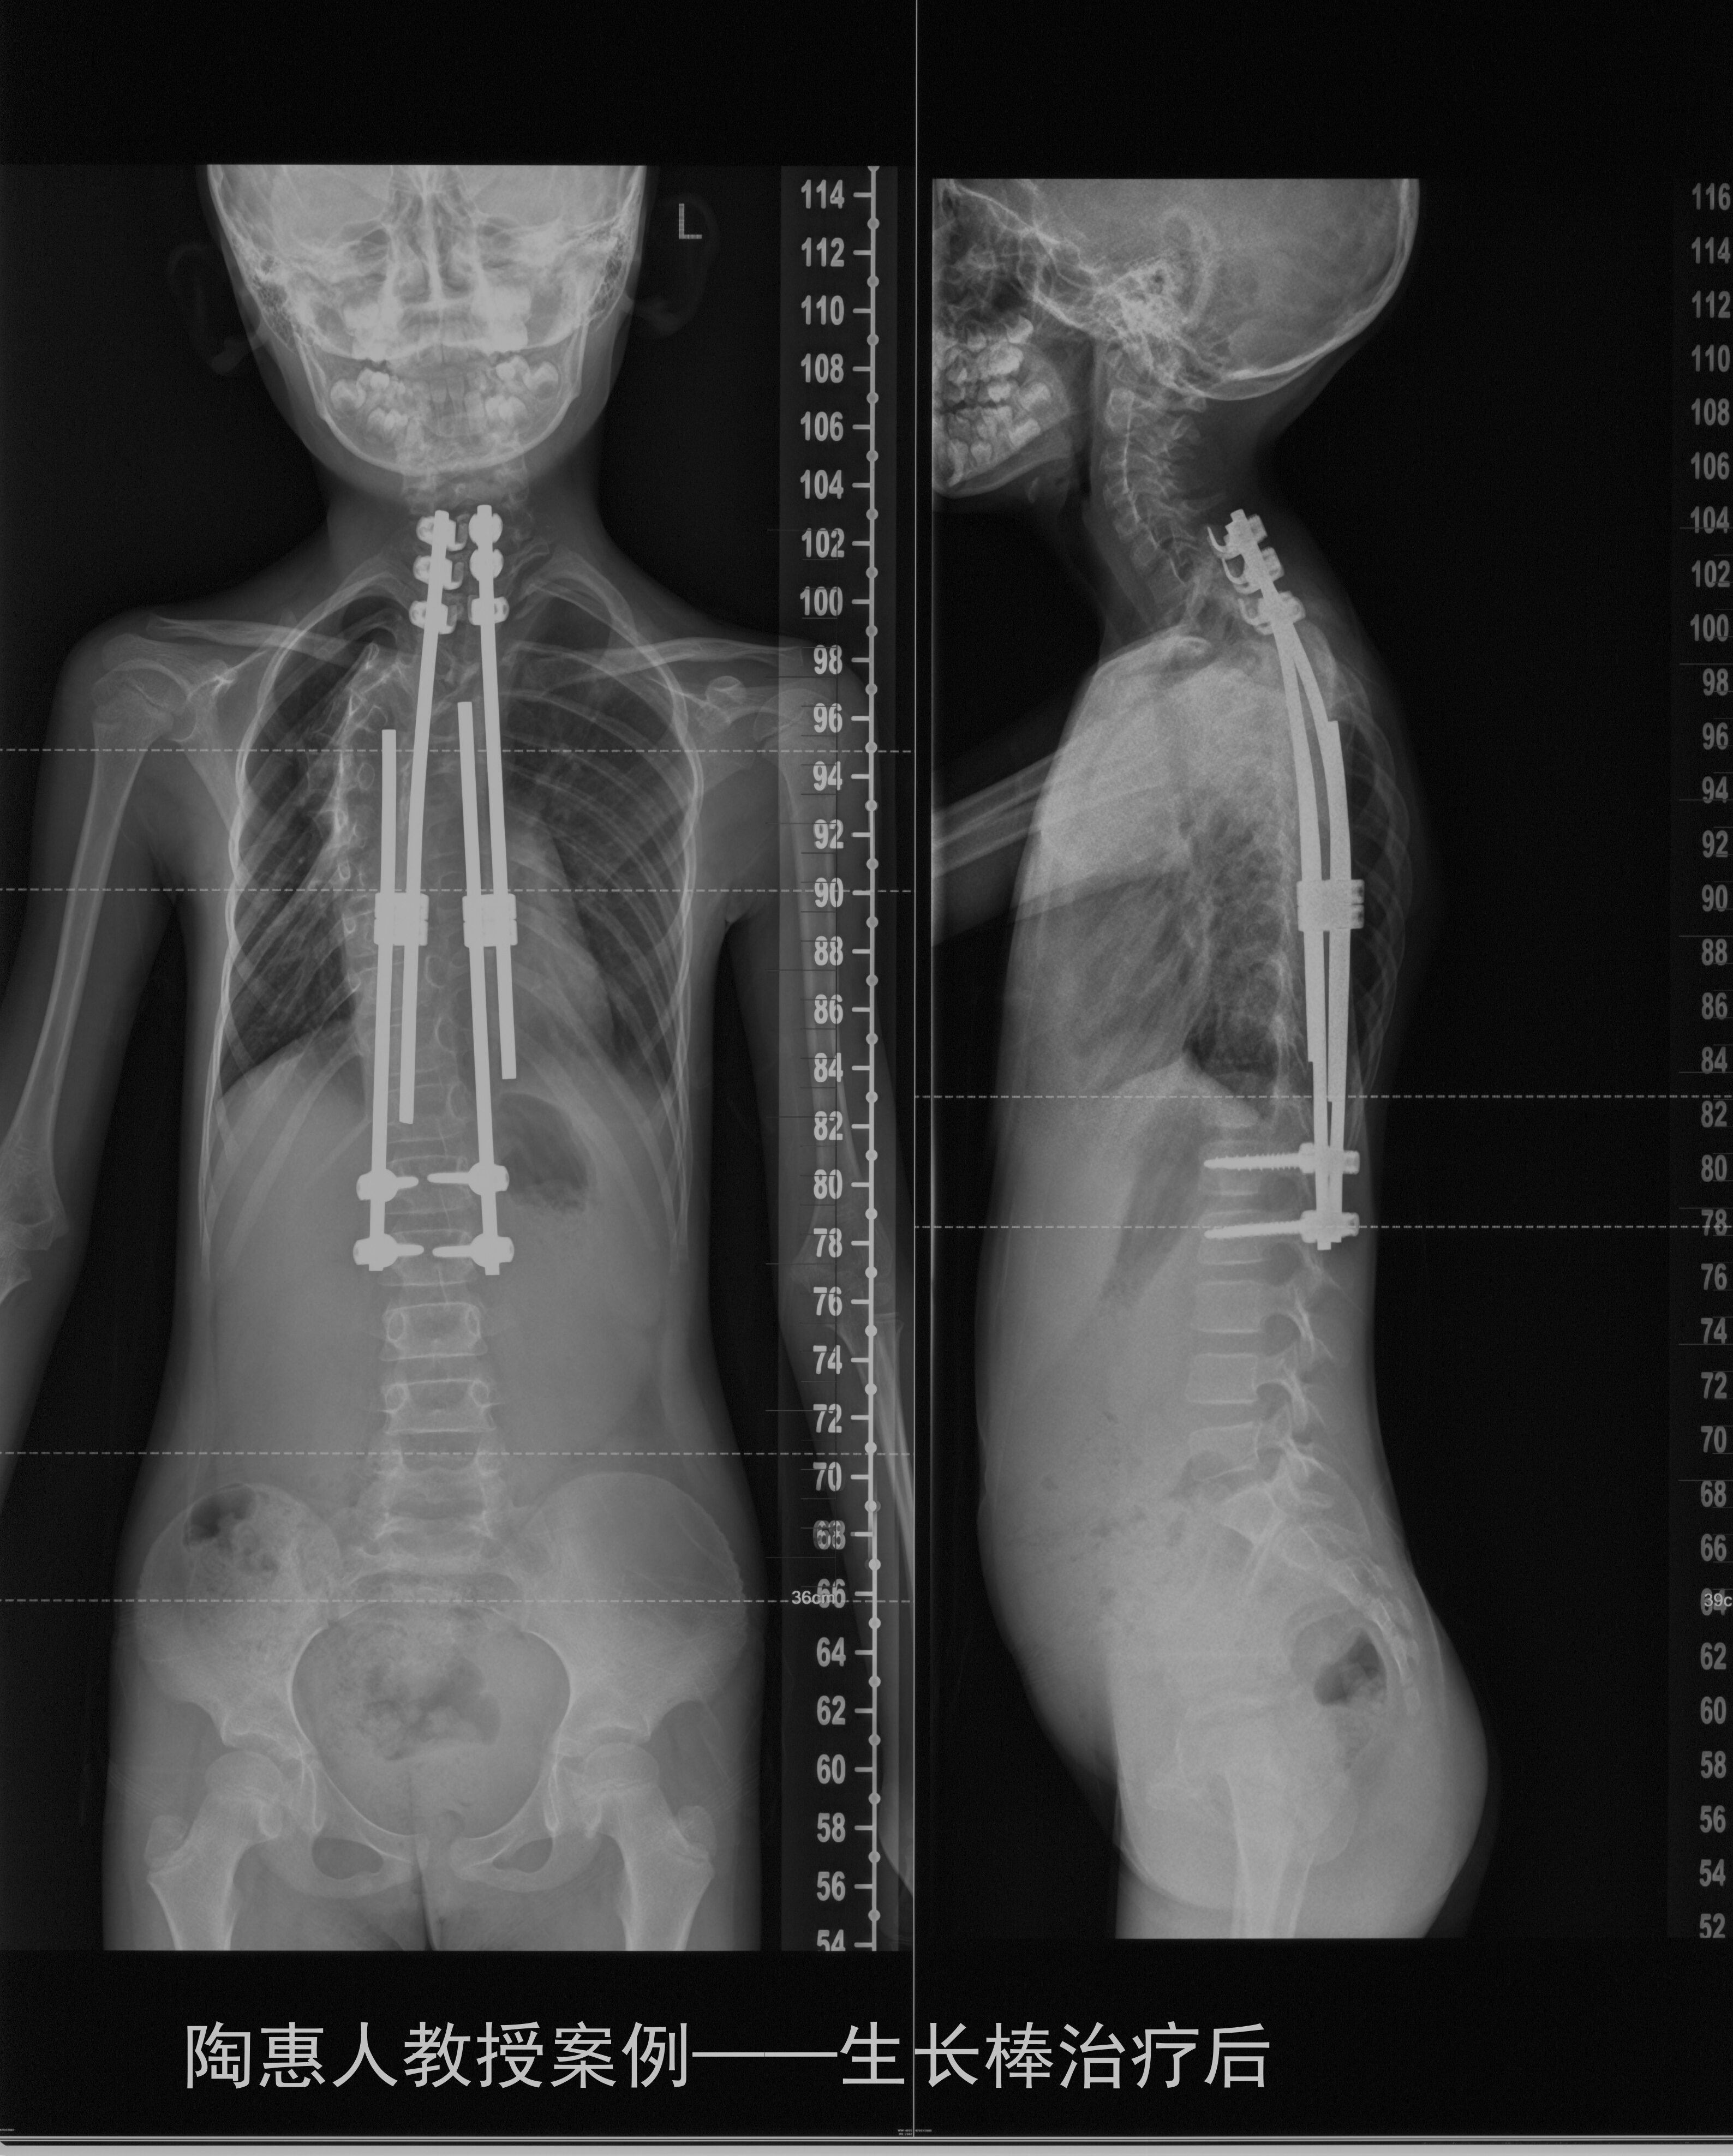

生长棒治疗就是用钛合金支架将脊柱撑直,但不进行截骨,这样骨骼不会被固定。然后每年依照患者生长情况进行一次或者两次撑开操作,每次撑开几厘米,让支架随着身高增加而延长。直到患儿十几岁以后,找一个合适的时机进行最后的融合手术。

这样既不影响患儿脊柱侧弯的治疗,又不会因为脊柱侧弯的治疗影响到患儿生长发育以及身高,因此受到患儿家属的推崇。

值得注意的是,这种生长棒治疗并不是一次手术就能实现的,需要每年甚至每半年做1次。患儿和家长也会在多次手术时承受心理及心理的压力,所以,需要做该手术的家长要有良好的心理准备,一切为了孩子的未来,让年幼的患儿接受手术的考验。